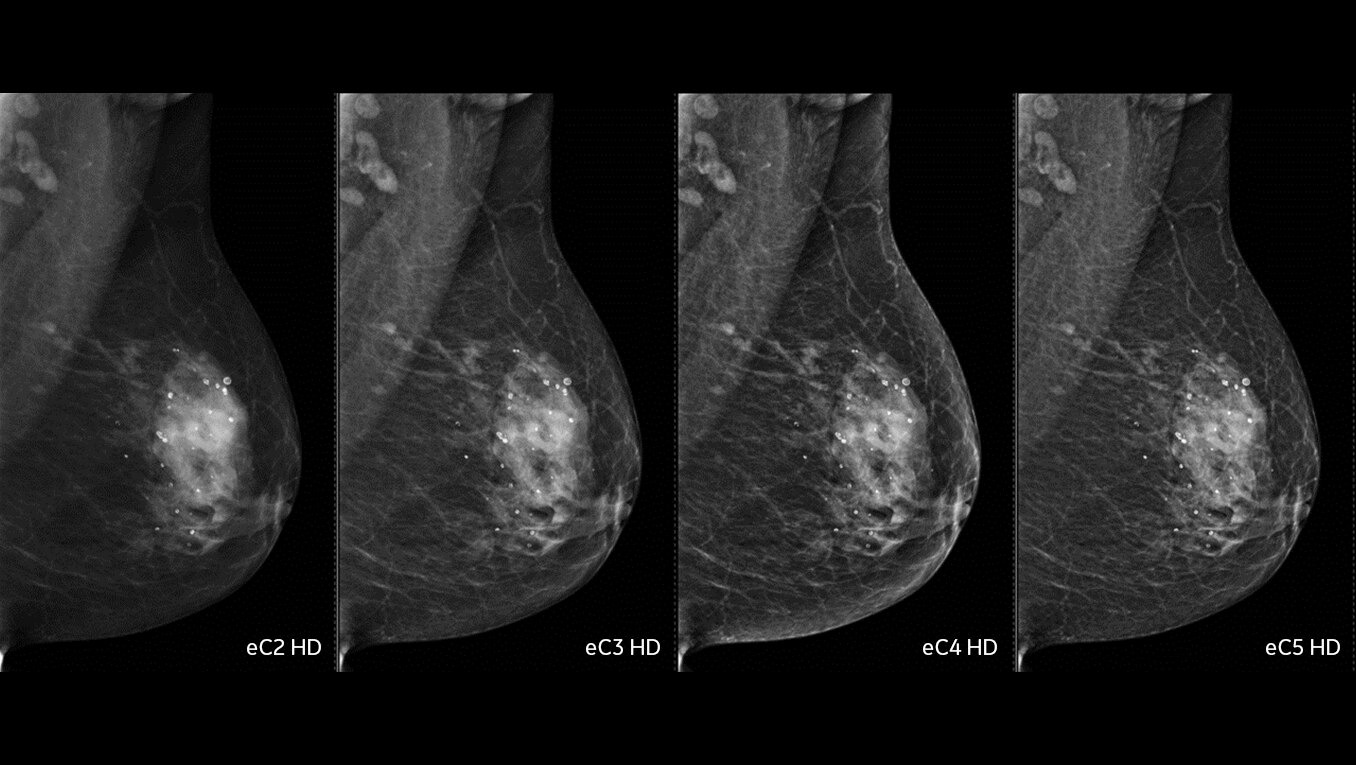

En el corazón de Revolution Advance se encuentra una cadena de adquisición de imágenes confiable y de alto rendimiento con 42 kW de potencia del generador, un tubo de rayos X de 3,5 MHU y detectores integrados que reducen la relación señal/ruido en un 20 %2. Esto va de la mano con nuestras aplicaciones inteligentes de reconstrucción de reducción de dosis, como ASiR2, que pueden proporcionar una dosis hasta un 40 % menor mientras se mantiene una alta calidad de imagen2.

En lo que respecta a la adquisición de imágenes de casos más desafiantes, como pacientes neurológicos, oncológicos o pediátricos, VISR3 (del inglés Volumetric Image Space Reconstruction, reconstrucción volumétrica del espacio de la imagen) reduce el ruido sin afectar la resolución de la imagen. Esto significa menos dosis para el paciente, a la vez que se mantiene la alta calidad de imagen que se necesita para diagnósticos más exactos.